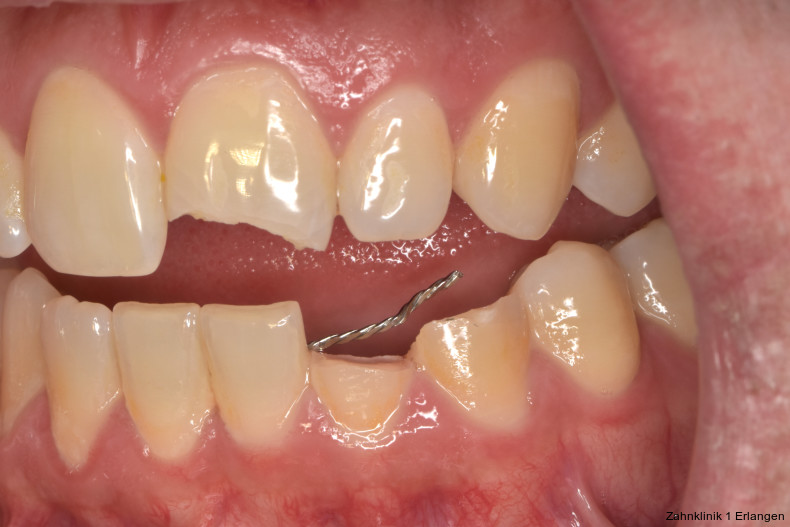

Versorgung von Dislokationsverletzung

Bei ausgeprägten Dislokationsverletzungen stellt die Schädigung des Parodonts die dominierende Verletzung dar, die auch zu Spätfolgen und Komplikationen führen kann. Verletzungen des Endodonts sind im Hinblick auf den Zahnerhalt vergleichsweise unbedeutender, da die Wurzelkanalbehandlung eine Infektion relativ sicher verhindern oder beseitigen kann. Die Erstversorgung schließt im Wesentlichen die Repositionierung und Schienung zur Ruhigstellung der betroffenen Zähne ein.3 Spätestens ab einer Positionsveränderung von 2 mm ist bei Zähnen mit abgeschlossenem Wurzelwachstum sicher von einem irreparablen Schaden der Pulpa auszugehen.2 Wichtig ist es, zeitnah, in der Regel während der Schienungsdauer, die Wurzelkanalbehandlung einzuleiten, um eine bakterielle Besiedelung des Wurzelkanals zu verhindern. Dabei reicht es zunächst aus, den Zahn zu eröffnen, desinfizierend zu spülen und eine medikamentöse Einlage einzubringen. Wird dies unterlassen, entwickeln sich bei entsprechender parodontaler Schädigung infektionsbedingte Resorptionen, die rasch fortschreiten und innerhalb relativ kurzer Zeit bis zum Zahnverlust führen können.